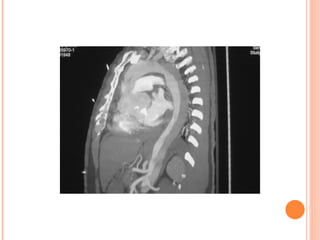

CT  - Highly sensitive - Requires stable patient for transport -Better than ultrasound at detecting rupture and retroperitoneal blood MRI or aortography are rarely indicated in the ED. Sharma U, Ghai S, Paul SB, Gulati MS, Bahl VK, Rajani M, Mukhopadhyay S. Helical CT evaluation of aortic aneurysms and dissection: a pictorial essay. ClinImaging. 2003

Computed tomography scan of ruptured abdominal aortic aneurysm, with calcification of the aortic wall and intraluminal thrombus. The patent lumen enhances with the administration of contrast material, but the periaortic hematoma   ( arrow )   does not .

Computed tomography scanof ruptured abdominal aortic aneurysm, with calcification of the aortic wall and intraluminal thrombus. The patent lumen enhances with the administration of contrast material, but the periaortic hematoma ( arrow ) does not .